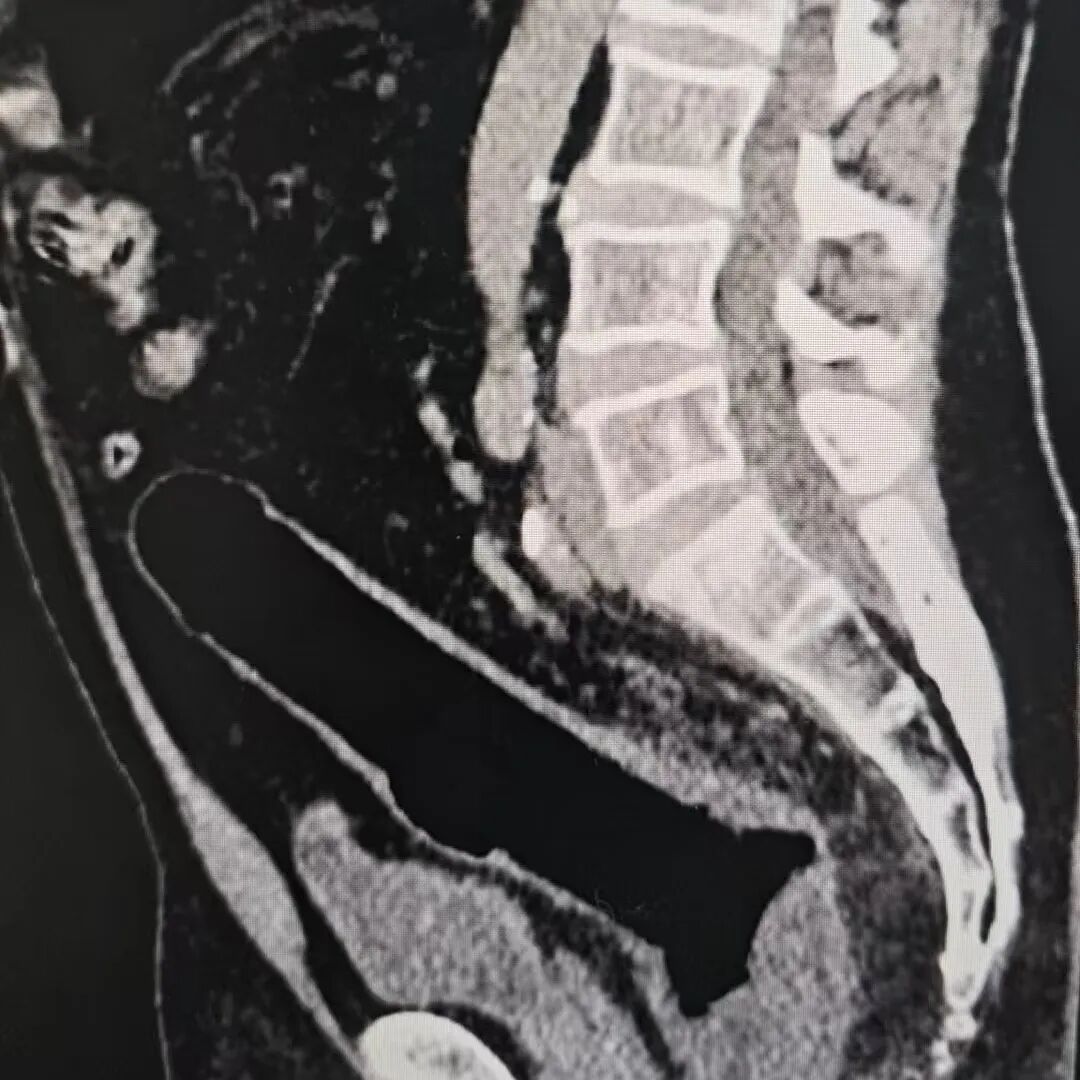

谁知两三天往日,异物不仅莫得排出,患者还出现了显著腹痛。再次就医作念 CT 查验后,恶果知道肠谈如故穿孔,正本通俗的异物取出问题,透澈演变成了急症。